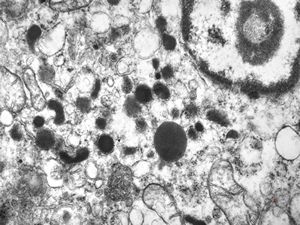

F, 71y. | carcinoid … metastasis to lymphonode